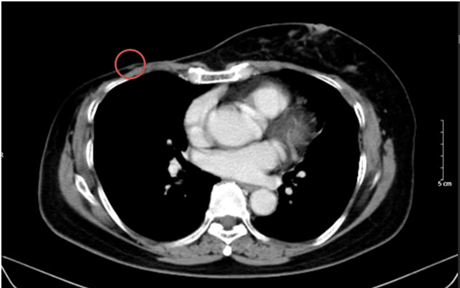

– Chụp cắt lớp vi tính bụng: Theo dõi dày khu trú tuyến thượng thận trái tạo nốt đường kính khoảng 9mm

Hình 3. Hình ảnh chụp CT bụng trước điều trị: Nốt tuyến thượng thận trái

– Chụp cắt lớp vi tính bụng: Theo dõi dày khu trú tuyến thượng thận trái tạo nốt đường kính khoảng 9mm (không thay đổi)

Hình 6. Hình ảnh chụp CT bụng sau điều trị: Nốt tuyến thượng thận trái